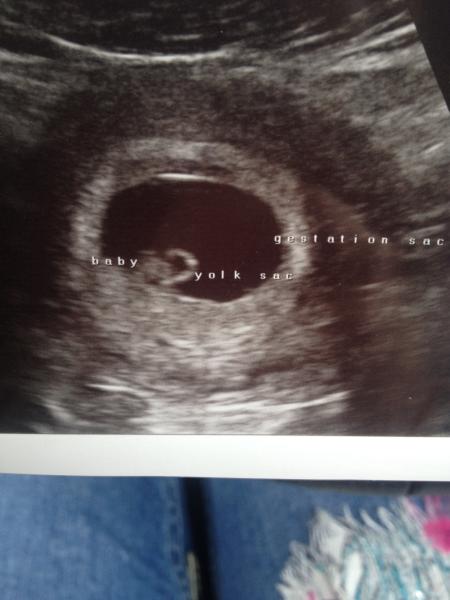

Measured me at 6+4 which is exactly what I thought! Saw a good strong heartbeat and got some little pictures of the blob! :-)